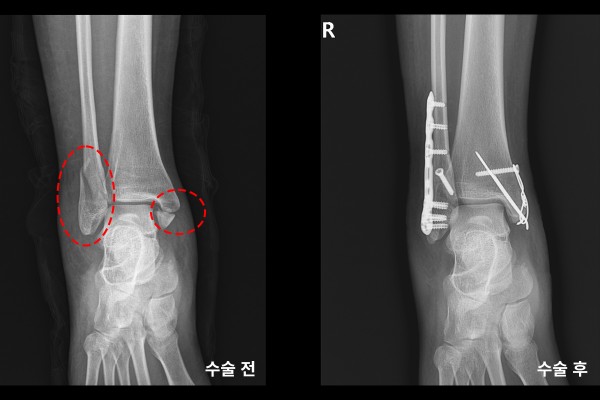

수술 후 X-RAY를 보면 잘 고정된 발목이 확인됩니다.

수술 전/후 X-RAY를 비교해보면 골절선이 잘 맞으며 수술이 잘 되었음이 한 눈에 확인됩니다.